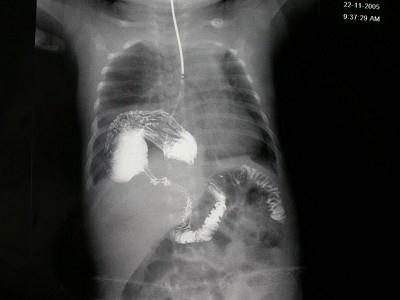

女,1岁,反复呕吐伴中度营养不良,结合影像,最可能的诊断为?(?)A.肺脓疡B.膈疝C.食道裂孔疝D.包裹性液气胸E.胃扭转

问题 女,1岁,反复呕吐伴中度营养不良,结合影像,最可能的诊断为?(?)

选项 A.肺脓疡 B.膈疝 C.食道裂孔疝 D.包裹性液气胸 E.胃扭转

答案 C